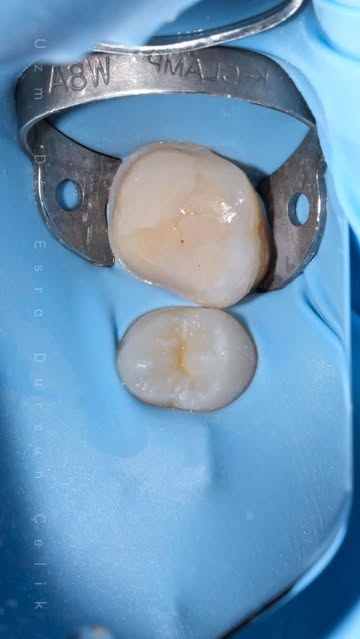

Uzman Diş Hekimi Esra Dursun Çelik, çocuklarda yapılan diş tedavilerinin uzun vadeli başarısının sadece işlemlere değil, ailelerin bakım ve beslenme konusundaki hassasiyetine ve düzenli kontrollerin aksatılmamasına bağlı olduğunu vurguladı. Ege adlı bir çocuğun genel anestezi altında yapılan tedavisinin üzerinden 4

- 5 yıl geçmesine rağmen kontrolünde yeni çıkan daimi dişlerinin de sağlıklı ve güçlü olduğunun görülmesi, bu durumun önemini bir kez daha ortaya koydu.

Çocuklarda diş sağlığını korumak için düzenli kontroller büyük önem taşıyor. Uzman Dt. Çelik, Ege’nin ailesinin Ankara’da yaşamasına rağmen şehir dışından her kontrole düzenli olarak gelerek örnek bir takip gösterdiğini belirtti. Bu düzenli takip sayesinde hem tedavi edilen dişlerin hem de yeni çıkan daimi dişlerin sağlığı korunuyor.

Başlarda röntgen çektirmekte zorlanılan Ege’nin ilk kontrol röntgeni 9 ay sonra alınabilmişti. Ancak bugün diş sağlığını korumak için büyük bir uyum ve özgüvenle kontrollerine geliyor. Bu durum, erken teşhisin ve düzenli takibin önemini gösteriyor.